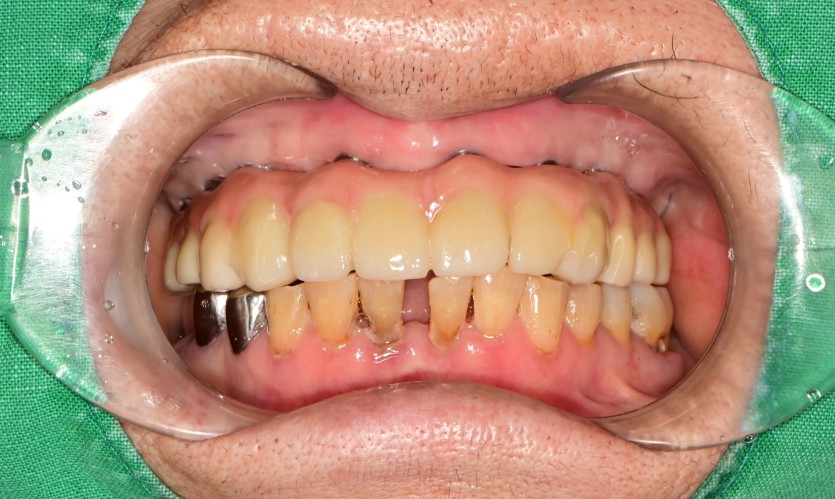

상악 풀아치 증례입니다.

8개의 임플란트로 완성하였습니다.